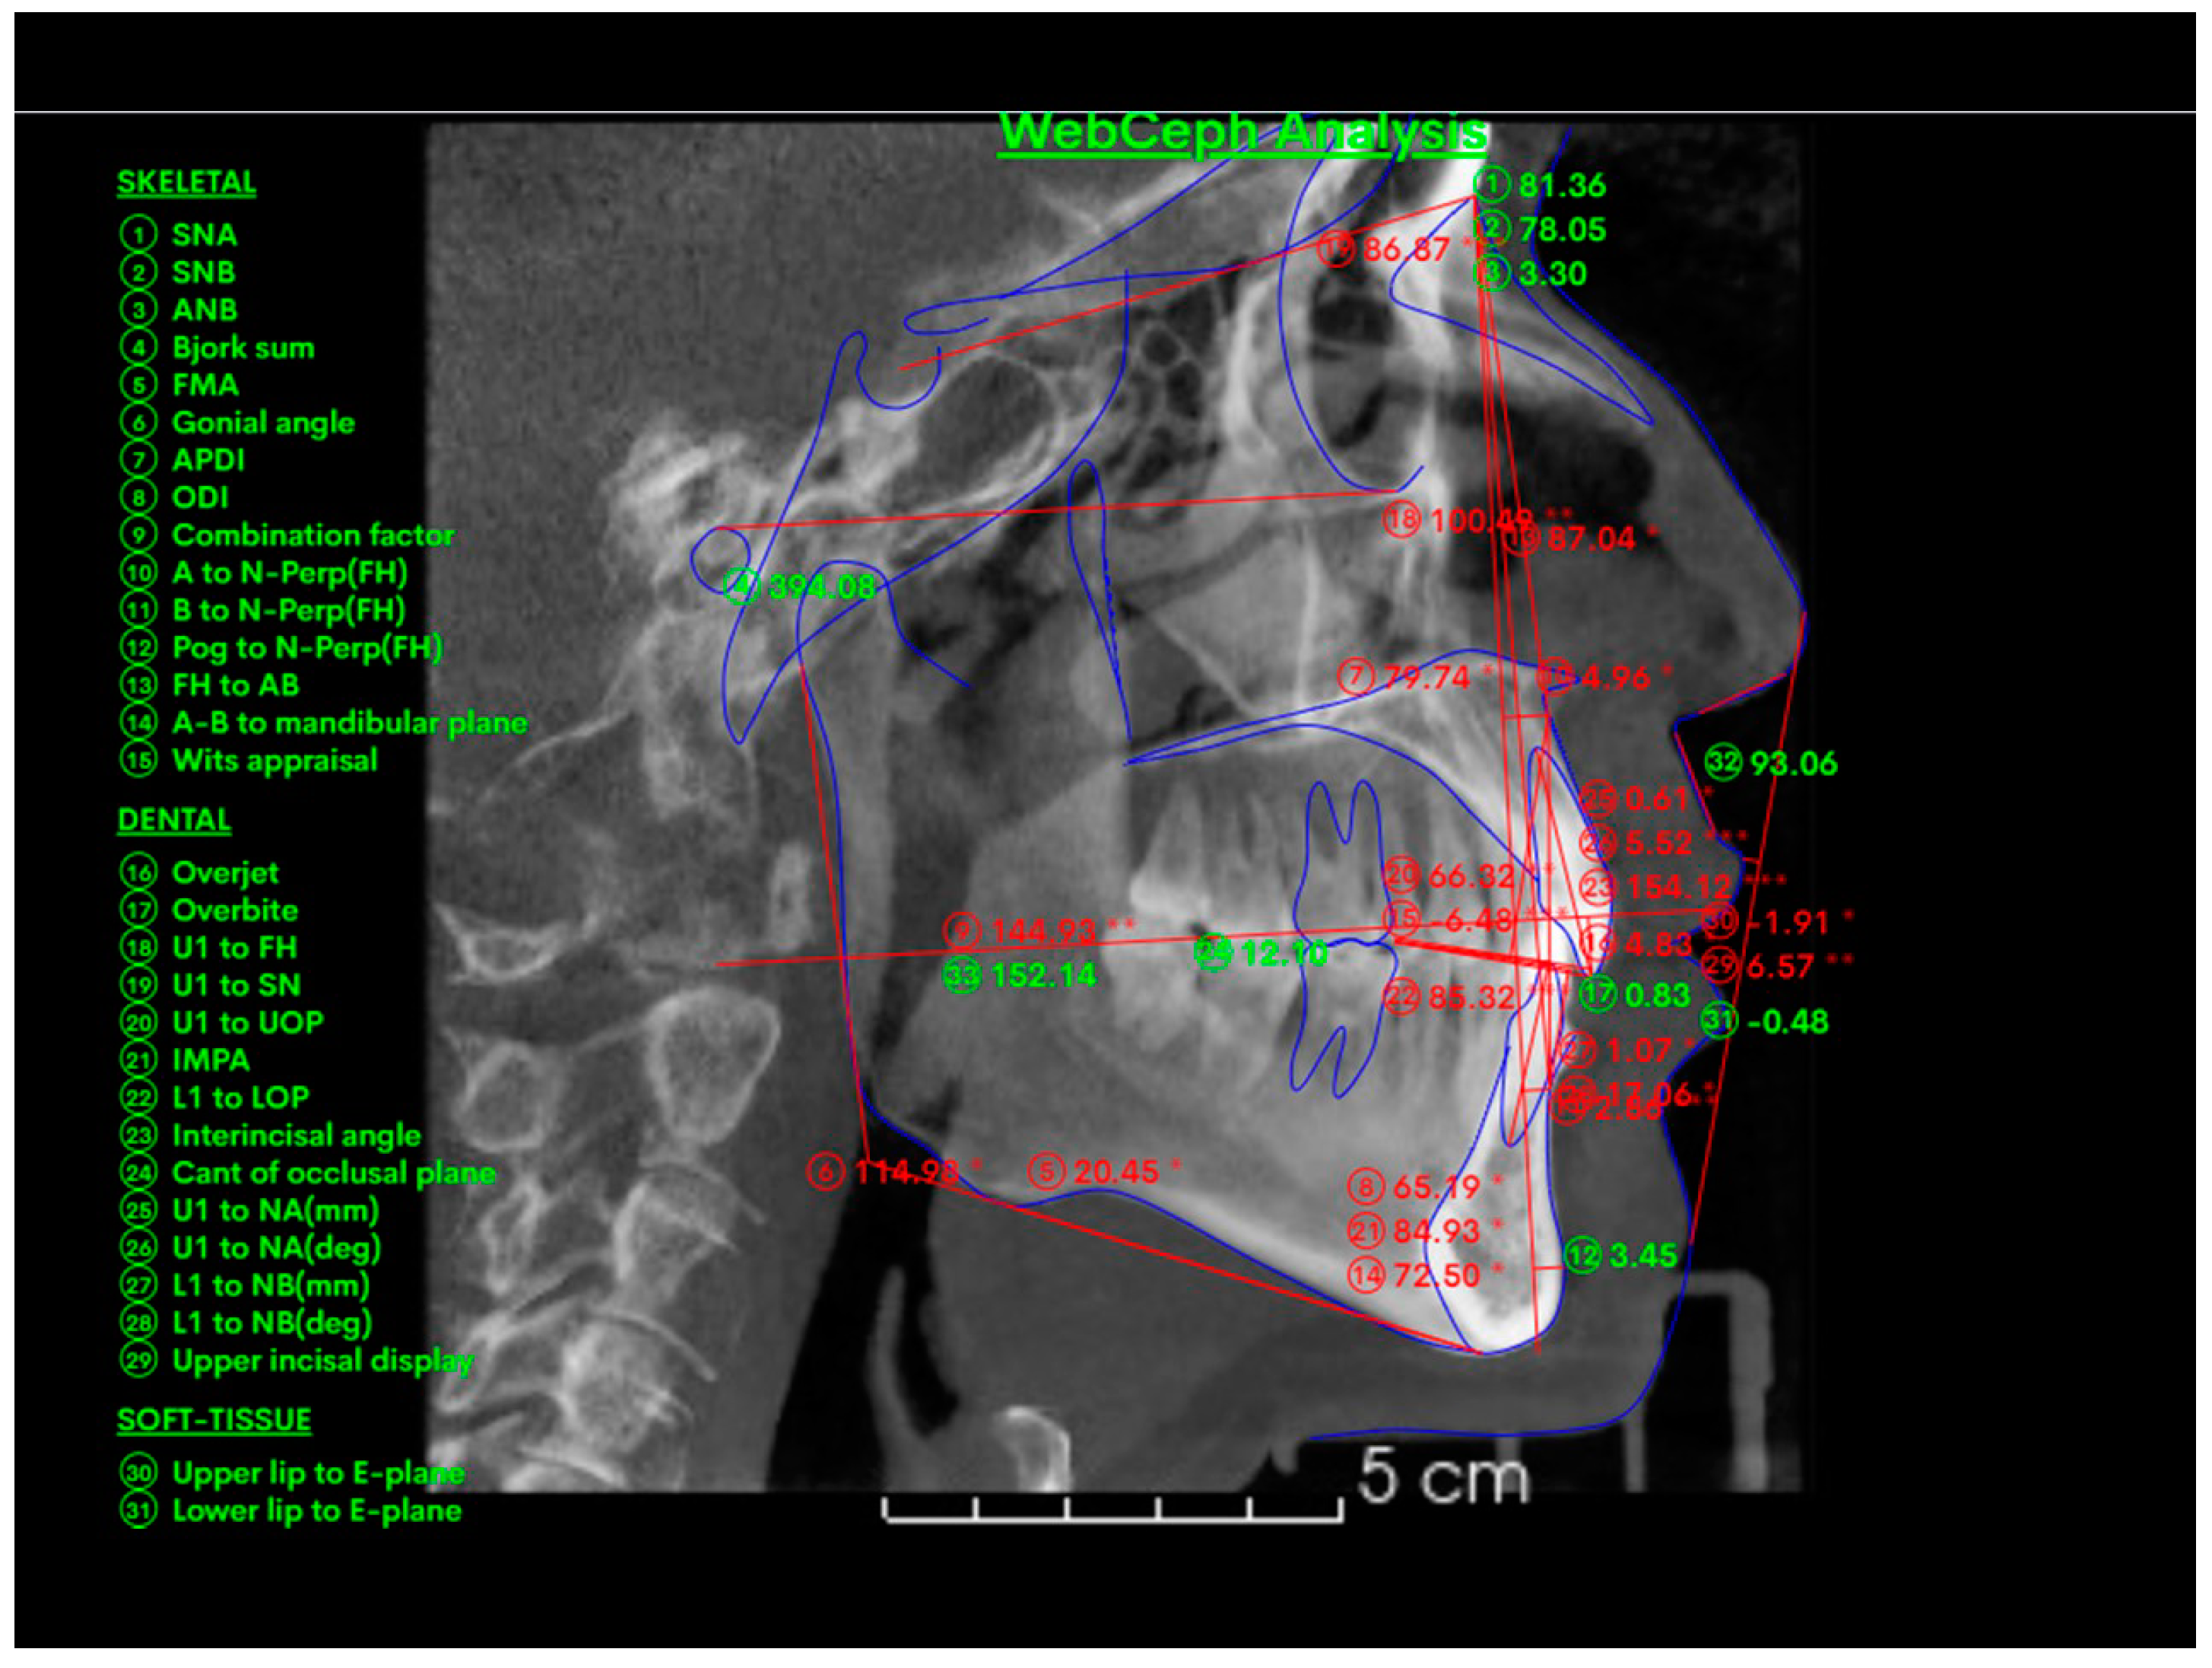

2.5. Cephalometric 2D Variables